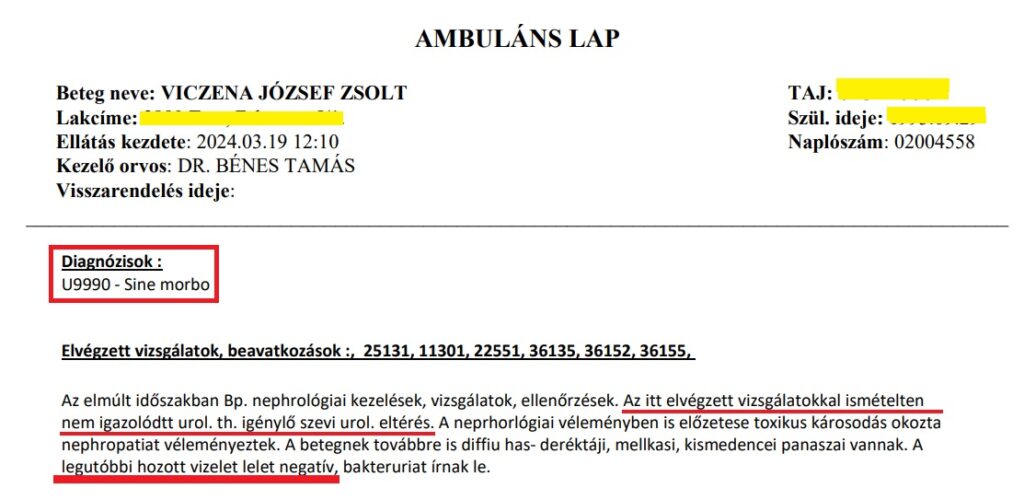

14./ Március 18. Petz Aladár Oktatókórház: 10 pozitív eltérés vizeletben = Sine Morbo

Mivel Ledó Nóra megtagadta a kezelést, visszatértünk a győri urológiára, ahol kezdtük másfél hónapja. Borzalmas „ötlet” volt. Itt a konzultáción kifogtuk ugyanazt a Dr. Bénes Tamást, aki súlyos vérvizeléssel és az akut állapottal 2024. február 9-én „kitette” a kórházból a fiamat. Ezúttal is ez történt, most így: a 10 pozitív értéket és veseelégtelenségi adatokat mutató leletre azt a hamis állítást merte tenni, hogy „Legutóbb hozott vizelet lelet negatív”. Így már leírhatta a Sine Morbo (=betegség nélküli) orvosi diagnózist a fiam ambuláns lapjára. Miközben mint fentebb csatoltuk, szinte nem volt negatív sor az adott vizeletleletben, és 13-a óta más vizeletvizsgálat nem készült, tehát azt minősítette Sine Morbo-nak. És küldte el ismét a fiamat, aki táskákkal érkezett kórházba, biztosak voltunk benne, hogy felveszik.

A másik orvos, akinek súlyos felelőssége van a fiam sorsáért, az Dr. Bénes Tamás, akihez először fordult a fiam segítségért az egyik legsúlyosabb és legfrissebb leletével, majd kitette az utcára. A második alkalommal egy 10 pozitív eredményt mutató SOTE-n készült vizeletleletet negatívnak minősített, csak hogy ráírhassa a leletre, hogy nincs urológiai ok, amit kezelni kellene, SINE MORBO (=egészséges). Amint kijött az orvosi szobából, a fiam szólt neki, hogy hogy lenne már SINE MORBO, amikor 10 súlyos pozitivitás van a leletben? – Mire Bénes továbbment és hátrakiabált: „Akkor tépje össze!” és lelépett.